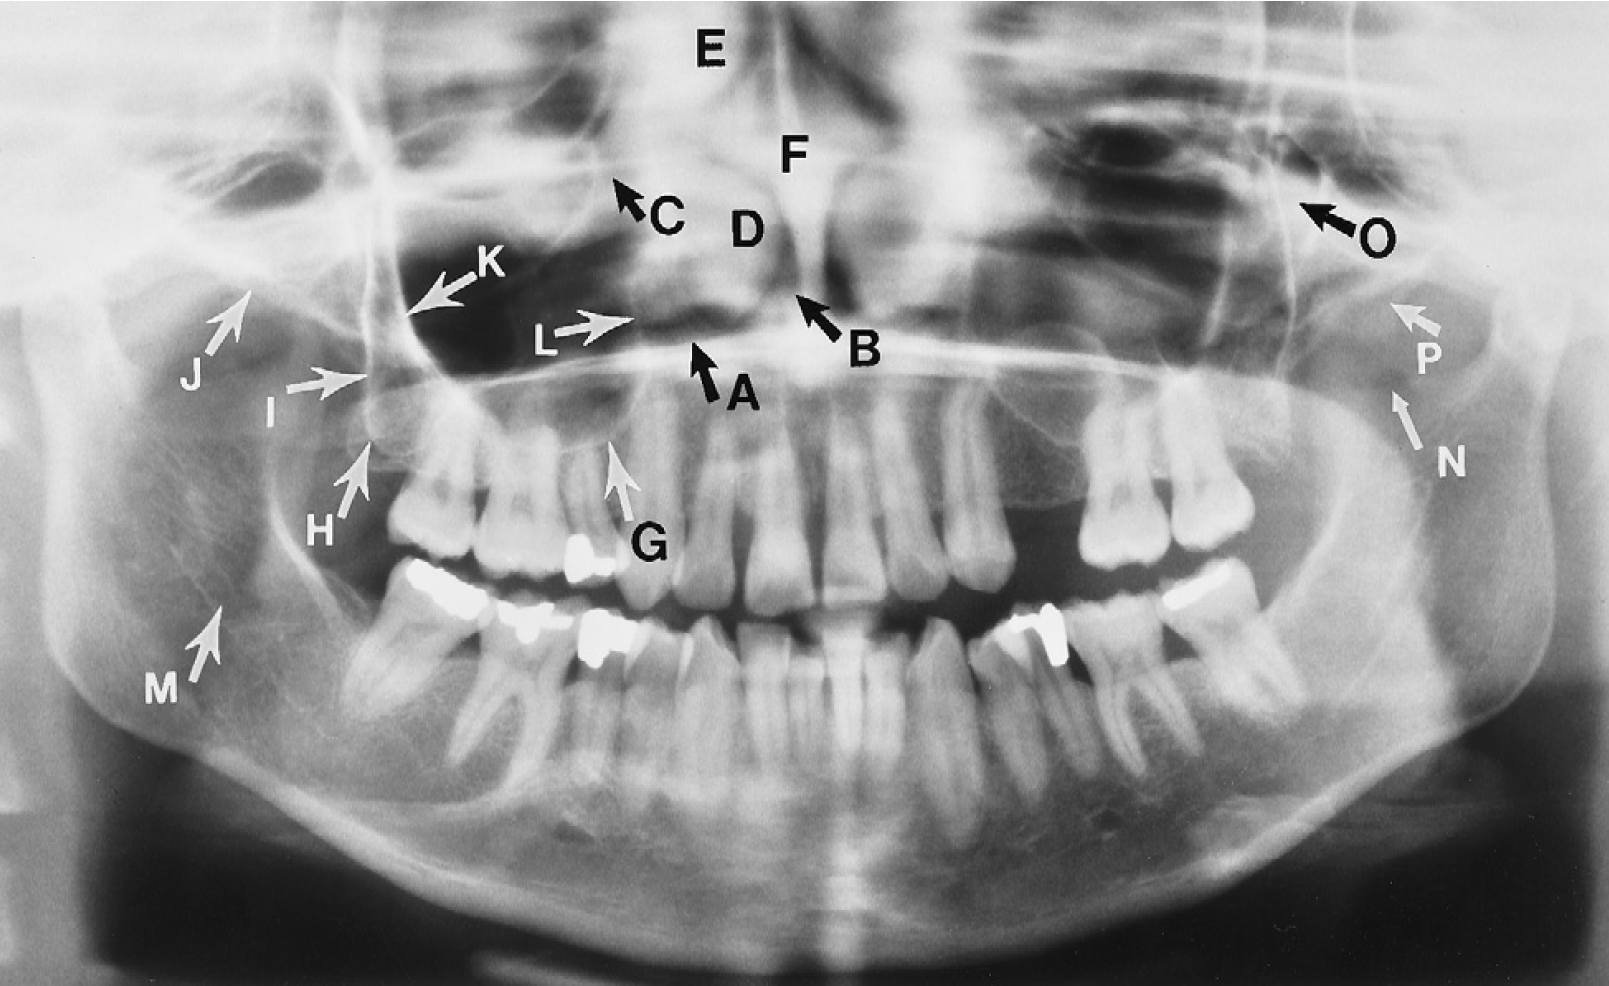

Anatomical Landmark Identification Quiz